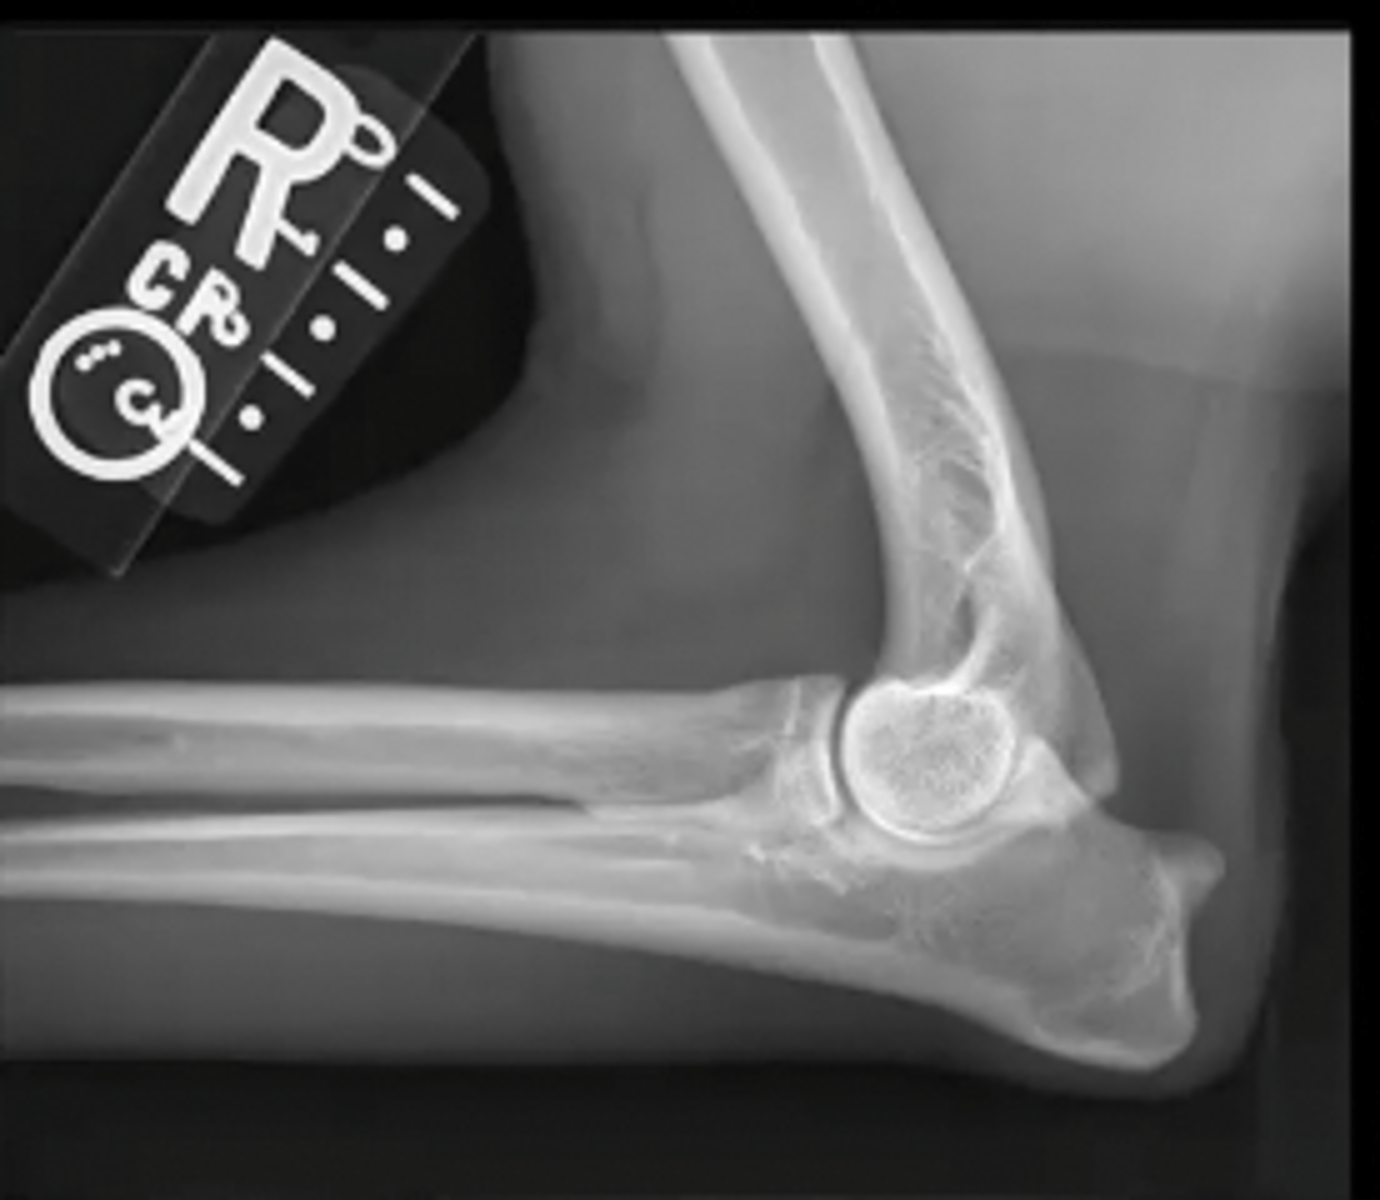

lateral canine elbow

What is the view of this image?